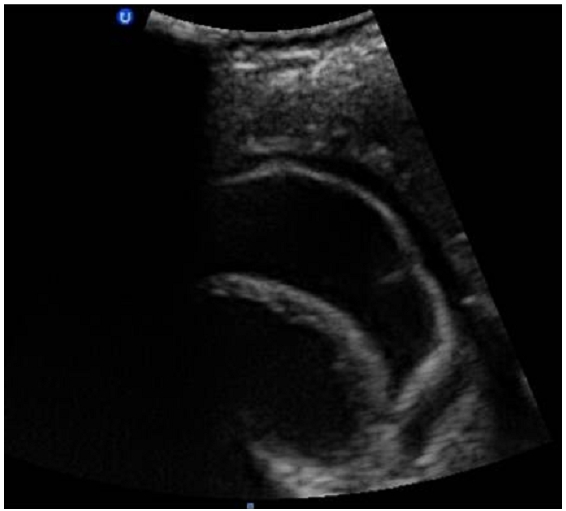

Figure 3.

Image d’échographique abdominale, montrant chez notre patiente de 23 ans, admise pour état de choc sur aménorrhée de 8 semaines, un kyste hépatique du segment III affaissé, avec membrane décollée témoignant de sa rupture et faisant évoquer en premier selon le contexte et les autres lésions hépatiques associées, un kyste hydatique rompu